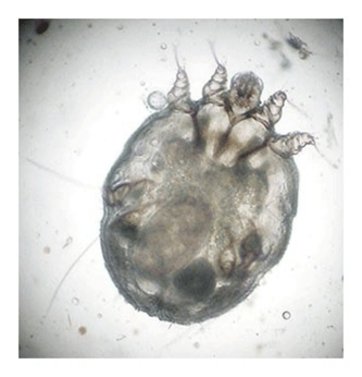

Fnatmiden Sarcoptes scabiei

Fnatmiden Sarcoptes scabiei graver gange under huden og lægger æg.

Fnat er en hudsygdom, som skyldes en såkaldt scabiesmide. Fnat kaldes derfor også scabies. Scabiesmiden graver små gange og lægger æg i huden på mennesker, og det giver en stærk kløe, som føles værst om natten.